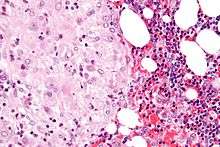

The decidua has a histologically-distinct appearance, displaying large polygonal decidual cells in the stroma. These are enlarged endometrial stromal cells, which resemble epithelium (and are referred to as "epithelioid").

Decidualization includes the process of differentiation of the spindle-shape stromal fibroblasts into the plump secretory decidual cells, which create a pericellular extracellular matrix rich in fibronectin and laminin (similar to epithelial cells).

Vascularity, as well as vascular permeability, is enhanced in the decidualizing endometrium.

Its leukocyte population is distinct, with the presence of large endometrial granular leukocytes being predominant, while polynuclear leukocytes and B cells are scant.